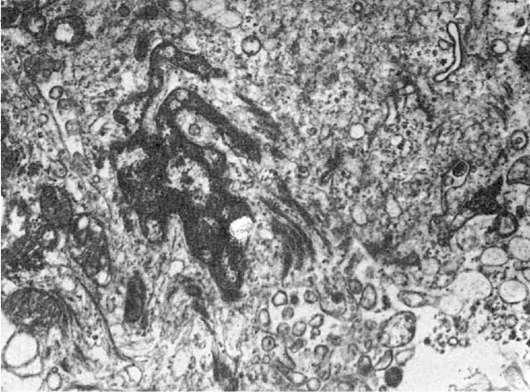

Другую группу наследственных болезней, обусловленных нарушением функции лизосом,

можно связать снарушением мембранных взаимодействий органелл клетки, что приводит к образованию гигантских органелл, в том числе гигантских лизосом (рис. 19). Эта группа невелика: синдром Чедиака-Хигаси, так называемая циклическая нейтропения.

Рис.

19. Гигантские светлые лизосомы звездчатого ретикулоэндотелиоцита при врожденной недостаточности α-1-антитрипсина. х21 000